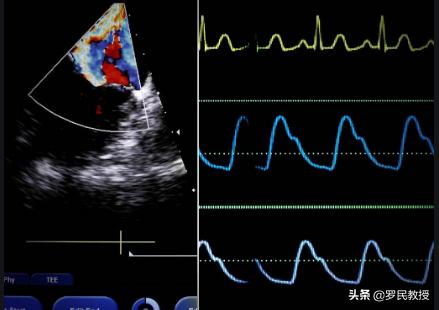

2、心臓超音波検査は心臓のような病気の検査で非常に重要であるが、すべての患者が行う必要はなく、主に心臓の構造と機能に焦点を当て、患者が先天性心疾患、拡張型心筋症、心不全などの問題がない限り、検査の結果が正常であることは珍しいことではない。

3、冠動脈造影は、欠落しているチェックの一つであり、それは冠状動脈性心臓病のゴールドスタンダードと呼ばれ、冠状動脈の血管の直感的なマルチアングル観察することができ、単純な息止め、胸の締め付けはもちろんのこと、患者がステントされている場合でも、超音波心電図正常である可能性があります。

2.心臓超音波

心臓を家に例えるなら、心電図で家の電気系統をチェックし、パイプが開いているかどうかを初期評価し、心臓超音波でドア、窓、壁をチェックする。心臓超音波検査と病気の成否に直接的な相関関係はない。超音波検査が正常であれば、心臓弁膜症、心筋症、心臓肥大、心不全などを除外することができる。